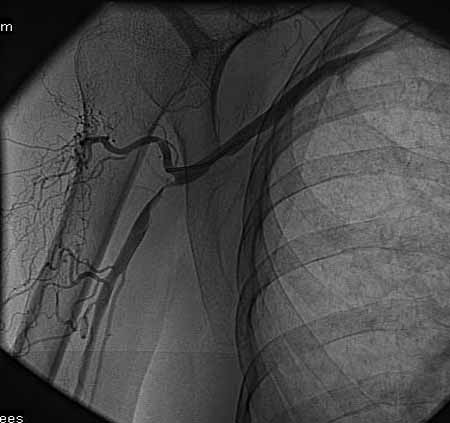

标题: DSA0091:肱动脉支架 [打印本页]

标题: DSA0091:肱动脉支架

女,66岁,右上肢无力.

馆主不错,图象清晰,栓塞处显示很清晰